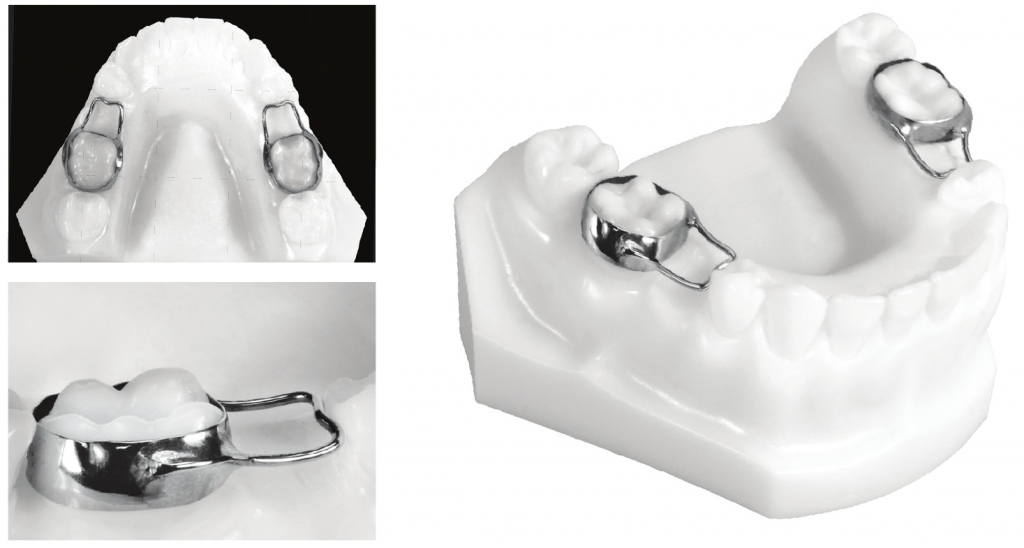

Band and loop – this device is most often used when the primary first molar is prematurely lost unilaterally. The second molar is banded, with the loop sitting against the distal surface of the canine. The band and loop is removed once the first premolar starts erupting. It can be used on other teeth. The most common reason stated for the failure of the appliance is cement failure and solder breakage. Crown and loop space maintainer – similar to a band and loop design but it has a higher survival rate.

Distal shoe – a modification of the band and loop, where one tooth (usually the adult first molar) is unerupted or partially erupted.